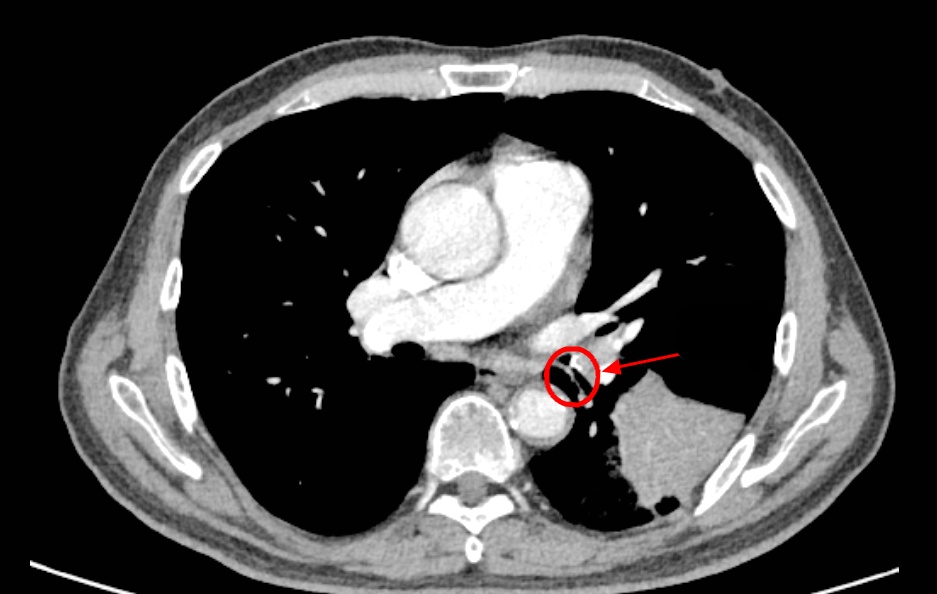

然而,从那天起,李老伯的咳嗽次数明显增多,而且还伴有浓痰,家人便带着李老伯到南京市第一医院河西院区呼吸与危重症医学科门诊就诊。胸部CT结果显示李老伯左肺下叶出现了一片“占位性病变”!

入院后,医生敏锐捕捉到一个关键细节:李老伯既往有明确的饮食后呛咳史,且此次发病前有吃鱼后呛咳的经历。因此判断,这应该不是肺部感染或肿瘤,高度怀疑是气道异物,要对李老伯进行支气管镜检查!

竟意外发现在一片因炎症而充血水肿的支气管黏膜中,一个细长、坚硬的异物正死死地卡在管腔内,周围包裹着大量的脓性分泌物。

原来竟然是一块长约1.6厘米的鱼骨!至此,真相大白。所谓的“肺部占位”,正是因为这块鱼骨堵塞气道,引发了堵塞性肺炎和肺不张,导致李老伯长达半个月的咳嗽和咳浓痰。